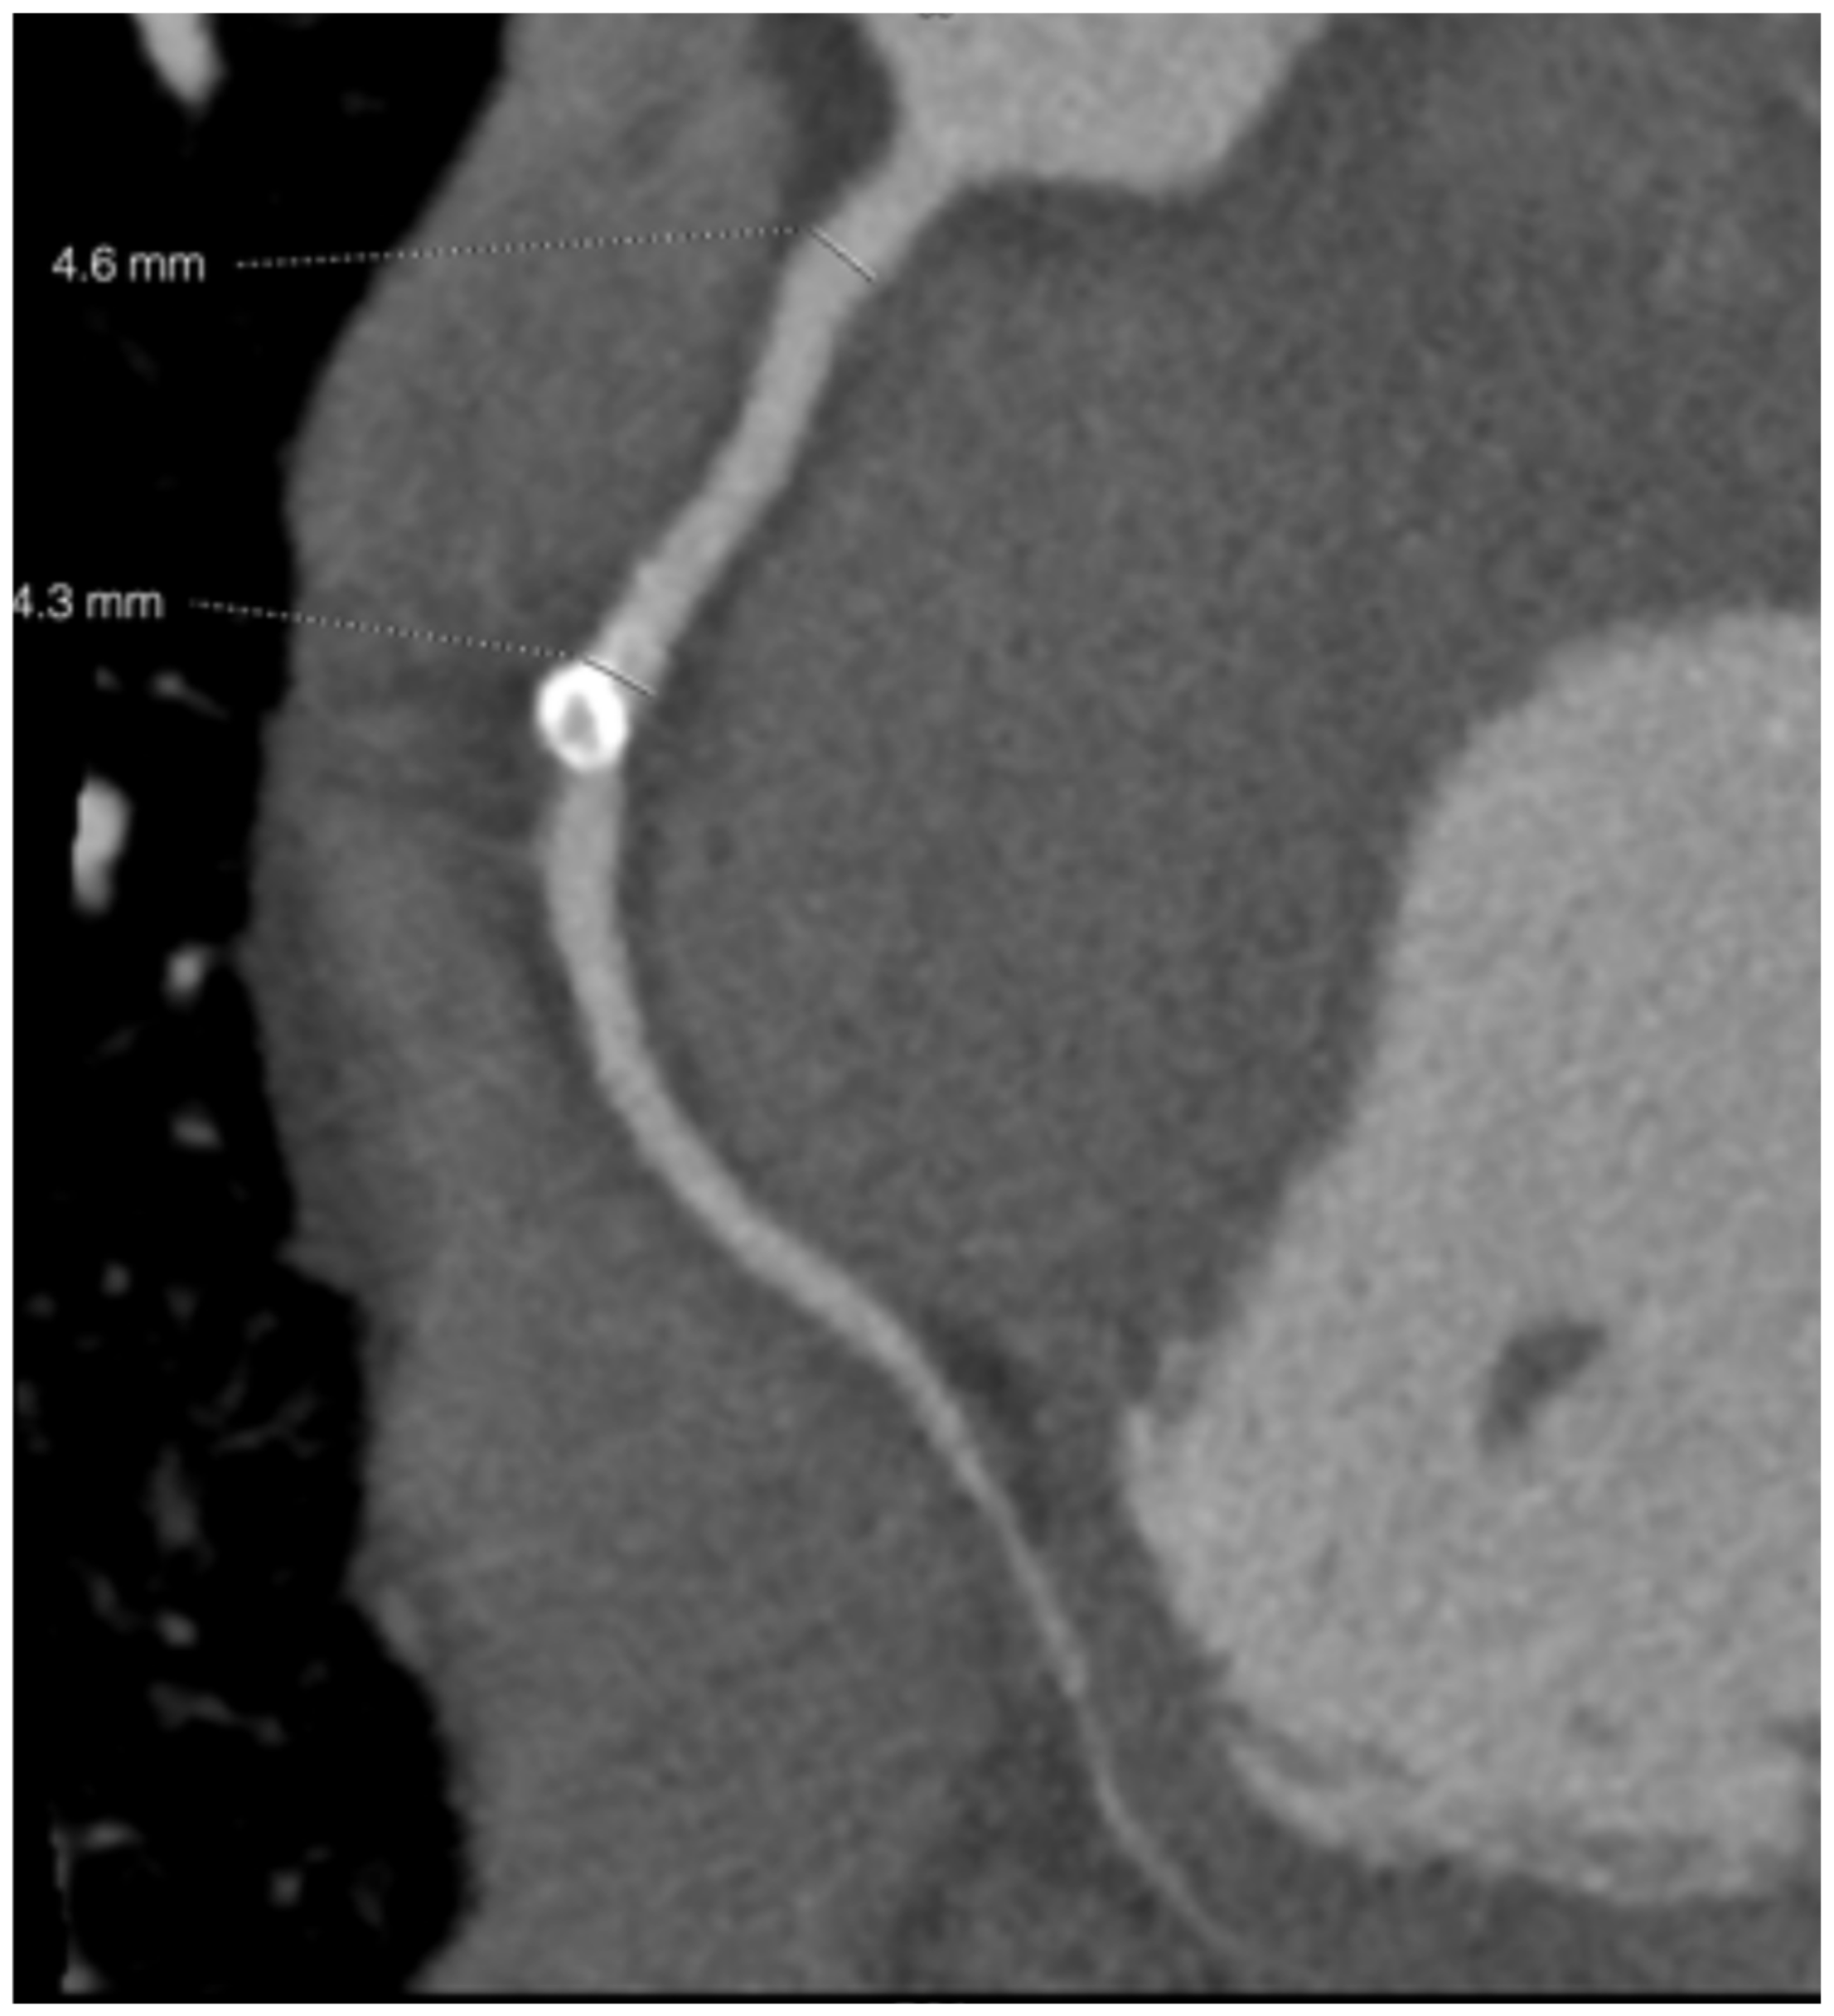

2. Case Report